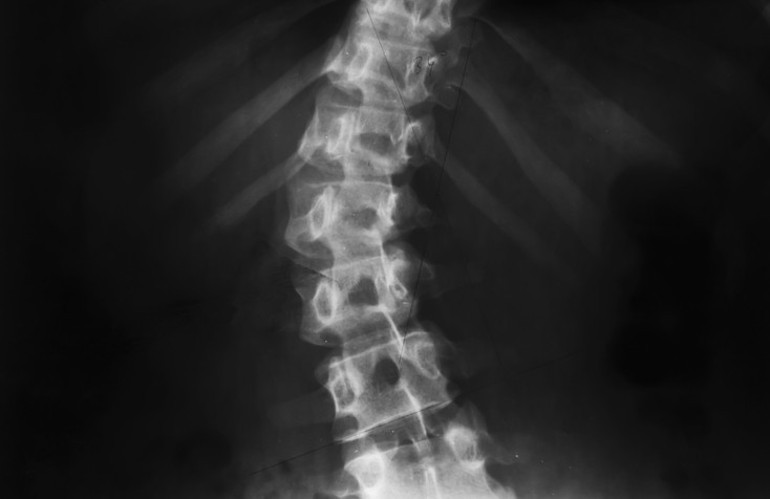

Skolyoz, omurganın göğüs veya bel bölgesinde yana doğru eğrilmesi durumudur. Sağlıklı bir omurga arkadan bakıldığında boyun, sırt ve bel boyunca düz bir çizgi oluşturur. Skolyozda ise omurlar yana kayar ve kendi eksenleri etrafında döner; bu da sırt ve duruşta belirgin asimetriye yol açar. Erken fark edildiğinde tedavi ve egzersizlerle ilerlemesi önlenebilir, bu nedenle ailelerin çocuklarının duruşunu düzenli olarak gözlemlemesi önemlidir.

Skolyoz çoğu zaman dikkatli bir gözle fark edilebiliyor. Omurgaya arkadan bakıldığında bazı eğrilikler düz durulduğunda net olarak görünmese de çocuk öne eğildiğinde, yapılan kontroller veya röntgen filmleriyle kolayca tespit edilebiliyor.

Ailelerin ve öğretmenlerin özellikle şu belirtilere dikkat etmesi gerekiyor; kalçalar veya omuz seviyelerinde eşitsizlik, kollar ile vücut arasındaki mesafenin bozulması, baş ve vücudun yana doğru kayması nedeniyle bacakların eşitsizmiş gibi algılanması, kız çocuklarında eteğin bir tarafının yukarı çekmesi, göğüs kafesinde asimetri ve kürek kemiğinde tümsek oluşumu. Bu işaretler, erken tanı ve tedavi için kritik öneme sahiptir.